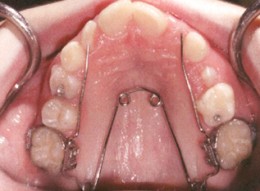

Le Quad Helix est un appareil qui sert à élargir la mâchoire supérieure. Il est composé de deux bagues placées sur les 2 premières molaires supérieures et d’une tige métallique qui passe au niveau du palais et qui est soudée aux bagues. Cette tige agit comme un ressort et élargit peu à peu la mâchoire.

vue du dessous